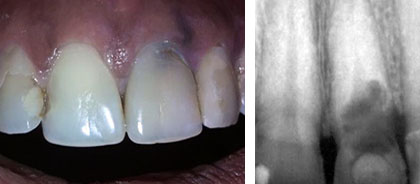

Paciente femenina con antecedentes de salud, de 31 años de edad y muy preocupada por su aspecto estético, quien acude a consulta por discromia en incisivo central superior izquierdo que impresiona necrosis pulpar. Al realizar acceso cameral se detecta sangramiento profuso del tejido existente en la cámara pulpar y al realizar radiografía periapical constata una reabsorción dentinaria interna que llegaba a la superficie externa de la raíz con destrucción de los tejidos periodontales adyacentes (Fig. 1).

Fig. 1 . Reabsorción dentinaria interna detectada al examen clínico y corroborada al examen radiográfico.